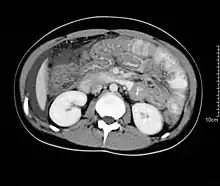

Spiral CT showing ascites and concentric thickening of colon and ileum in EG

Hypereosinophilia, the hallmark of allergic response, may be absent in up to 20% of patients, but hypoalbuminaemia and other abnormalities suggestive of malabsorption may be present. CT scans may show nodular and irregular thickening of the folds in the distal stomach and proximal small bowel, but these findings can also be present in other conditions like Crohn's disease and lymphoma.